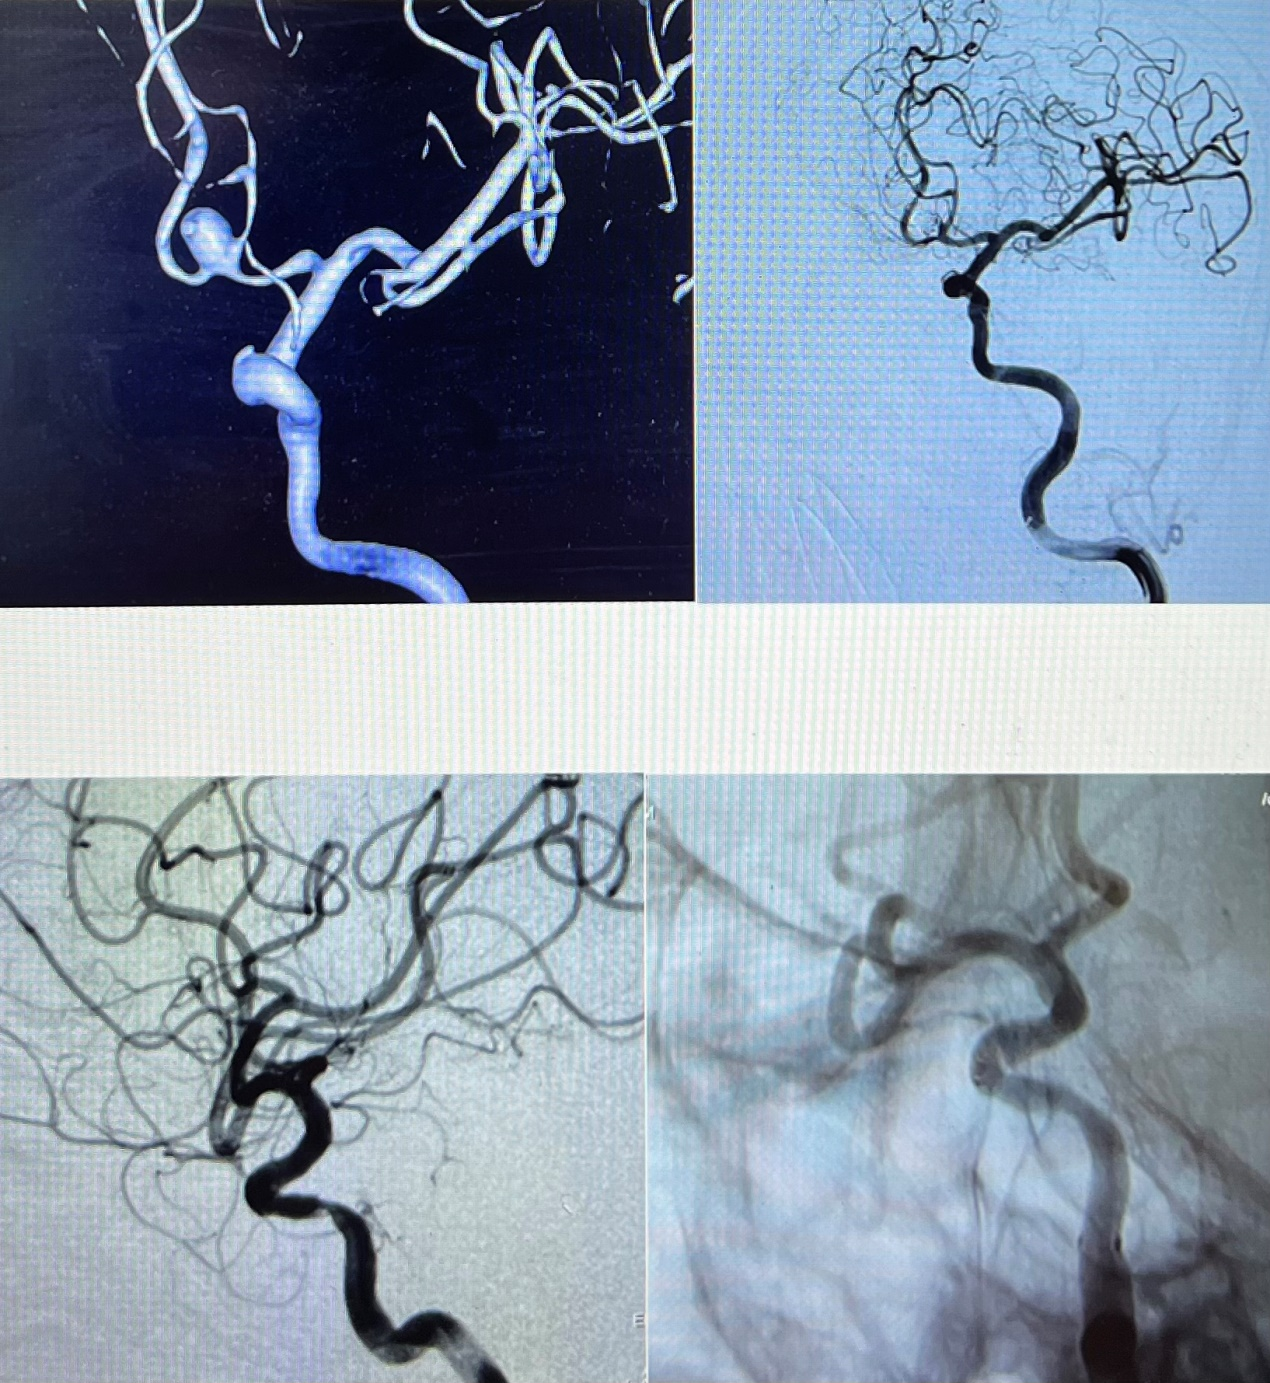

3月4日,1例自发性蛛网膜下腔出血患者紧急送入庆阳市人民医院急诊科,经检查,患者自发性蛛网膜下腔出血诊断明确,多考虑颅内动脉瘤破裂出血。庆阳市人民医院神经外科李争民主任有序协调,经过积极术前准备,在兰大二院陇东区域医疗中心帮扶庆阳市人民医院医疗队神经外科唐博副主任医师指导下,为患者行全脑血管造影,并在全麻下行“颅内动脉瘤栓塞术”,历时1个小时,手术顺利完成,患者顺利苏醒拔管。

6日,在唐博副主任医师的指导下,庆阳市人民医院神经外科又为1例前交通动脉瘤及1例颅内血管重度狭窄的患者成功实施了手术。